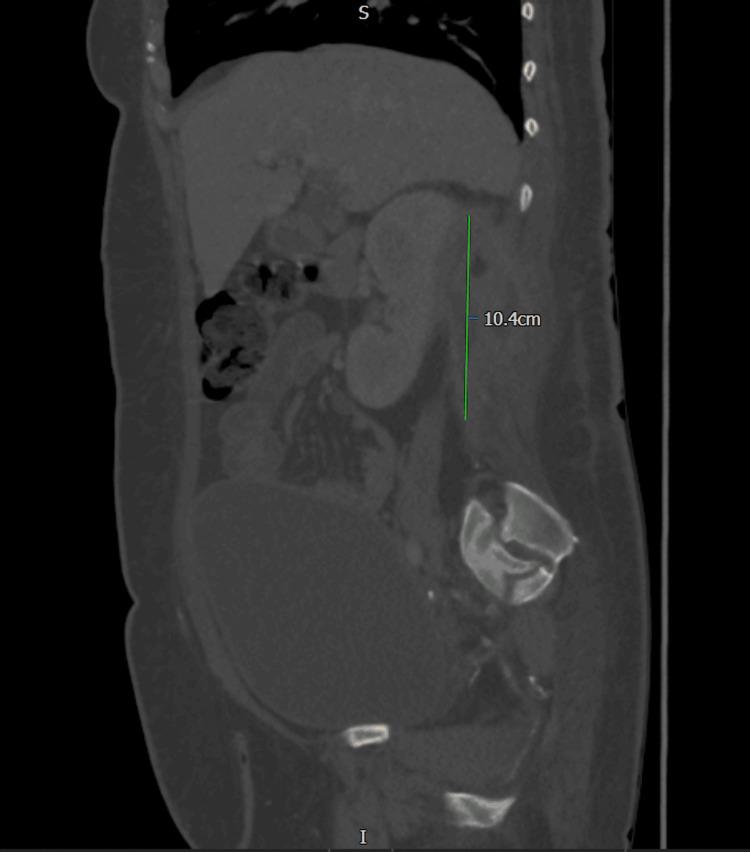

Iliopsoas abscess is a rare infection that presents with a triad of fever, back pain, and hip pain. However, due to the anatomical proximity of the psoas muscle to various structures, an abscess in this region can manifest with nonspecific symptoms, leading to potential misdiagnosis and delayed diagnosis, which can be fatal. We report a case of a 54-year-old female who presented to the emergency department with right-sided flank pain and symptoms resembling lower motor neuron disorder. Initial investigations were inconclusive until an MRI revealed a large retroperitoneal collection in the right perinephric space and iliopsoas muscle, likely of urological origin, with no spinal abnormalities. Intravenous gentamicin was initiated. A subsequent contrast-enhanced CT scan of the abdomen and pelvis confirmed a right posterior perinephric collection. Ultrasound-guided drainage was performed, and a pigtail catheter was placed in situ for continuous drainage along with targeted antibiotics based on culture and sensitivity.

髂腰肌脓肿是一种罕见的感染性疾病,表现为发热、背痛和髋部疼痛三联征。然而,由于腰大肌与各种结构在解剖位置上相邻,该区域的脓肿可能表现为非特异性症状,导致潜在的误诊和诊断延迟,这可能是致命的。我们报告一例54岁女性,因右侧胁腹疼痛及类似下运动神经元疾病的症状就诊于急诊科。最初的检查结果不明确,直到磁共振成像(MRI)显示右肾周间隙和髂腰肌有一个大的腹膜后积液,可能源于泌尿系统,且无脊柱异常。开始静脉注射庆大霉素。随后的腹部和盆腔增强CT扫描证实右肾后有积液。进行了超声引导下引流,并置入一根猪尾导管进行持续引流,同时根据培养和药敏结果使用针对性抗生素。